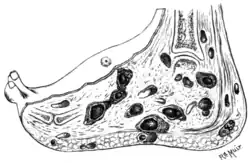

| An infected foot | |

Eumycetoma, also known as Madura foot,[1][6] is a persistent fungal infection of the skin and the tissues just under the skin, affecting most commonly the feet, although it can occur in hands and other body parts.[5] It starts as a painless wet nodule, which may be present for years before ulceration, swelling, grainy discharge and weeping from sinuses and fistulae, followed by bone deformity.[3]

The initial lesion is a small swelling under the skin following minor penetrating trauma (e.g stepping on broken glass) [11][12] It appears as a painless wet nodule, which may be present for years before ulceration, swelling and weeping from sinuses, followed by bone deformity.[3][7] The sinuses discharge a grainy liquid of fungal colonies.[11] These grains are usually black or white.[13] Destruction of deeper tissues, and deformity and loss of function in the affected limbs may occur in later stages.[14] It tends to occur in one foot.[13] Mycetoma due to bacteria has similar clinical features.[15]